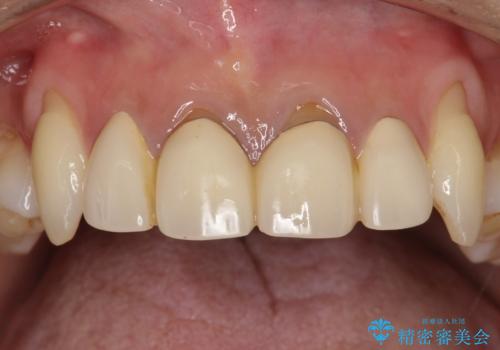

前歯の合計6本をオールセラミッククラウンにする計画としました。

一つ一つを独立したかぶせ物を装着することで、フロスも可能になり、清掃性が向上しました。